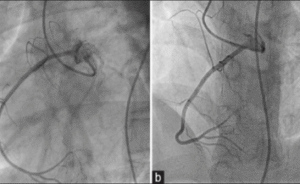

Coronary angiography is a minimally invasive imaging test that uses X-ray technology and contrast dye to visualize the coronary arteries. The procedure helps cardiologists detect blockages or narrowing that may restrict blood flow to the heart muscle.

How Is Coronary Angiography Performed?

- Catheter Placement: A thin catheter is guided to the coronary arteries

- Contrast Injection: Dye highlights the arteries on live X-ray imaging

- Imaging: Detailed images reveal blockages or abnormalities